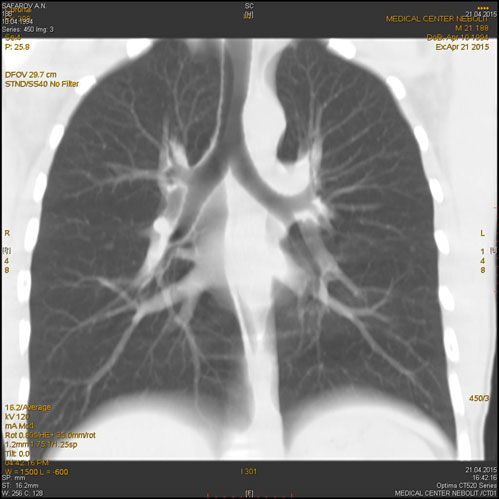

МСКТ органов грудной клетки (легких и средостения).Рентген является базовым методом исследования грудной клетки. МСКТ применяется в выявлении стадии рака легкого, туберкулеза, определяет структуру патологических образований, таких как киста, солидный компонент, сосудистые, жидкостные и воздушные полости, подозрение на ТЭЛА.

С появлением МСКТ уходит в прошлое КТ с высоким разрешением для диагностики интерстициальных заболеваний легких. При использовании МСКТ можно дифференцировать диффузные интерстициальные процессы в легких альвеолит, бронхиолит, саркоидоз, канцироматоз и очаговые изменения.

Астма и хронический бронхит диагностируются клинически. Половина больных с хроническим бронхитом имеют нормальную картину при рентгенографии. При МСКТ у пациентов можно выявить признаки обструкции-участки вздутия легочной ткани обусловленные закупоркой мелких бронхов, участки гиповентиляции за счет отека слизистой, эмфизематозные буллы, дисковидные ателектазы, бронхоэктазы.

Показания:

- Выявление изменений в легких не отображающихся на рентгенограммах

- подозрение на объемное образование легких, средостения, плевры, диафрагмы,

- лимфоаденопатия неясного генеза,

- синдром долевых и сегментарных затемнений, когда обычного рентгенологического исследования недостаточно для постановки диагноза

- для уточнения наличия очагов отсева или полостей распада при специфических поражениях легких и средостения

- аномалии развития бронхо — легочной системы

- воспалительные заболевания легких и средостения, осложнения пневмонии

- детализация диффузных изменений

- подозрение на разрыв расслоение аорты, хроническую эмболическую легочную гипертензию

- травма

- медиастинит

- опухоли пищевода

Предварительное рекомендуемое обследование: рентгенография грудной клетки

Подготовка:Не требуется.

Эмболии лкгочной артерии, источником которых обычно являются тромбы в венах таза и нижних конечностей являются грозным и относительно частым осложнением особенно у лежачих больных и после операции. Данные при рентгенографии неспецифичны. Без инфаркта может определяться приподнятие купола диафрагмы и сужение теней сосудов к периферии. Возможности МСКТ в диагностике ТЭЛА в ряде случаев позволяют отказаться от проведения инвазивной ангиографии.